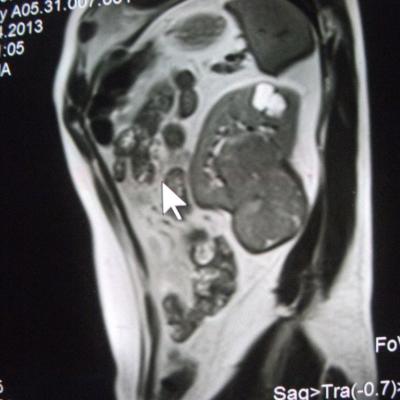

такое заключение: Левая почка: расположена обычно, увеличена, общими размерами около 13х5,5см. В области средней и нижней трети почки определяется объёмное образование неправильной формы, деформирующее наружный контур почки, распространяющиеся с чашечно-лоханочную систему. Опухоль имеет четкие неровные бугристые контуры с наличием псевдокапсулы, неоднородной структуры с признаками распада, максимальными размерами около 78,7х47х48мм

Вопрос такой: можно ли обойтись без удаления почки, удалив только опухоль.

Технически можно. Но практически - лучше нефрэктомия.